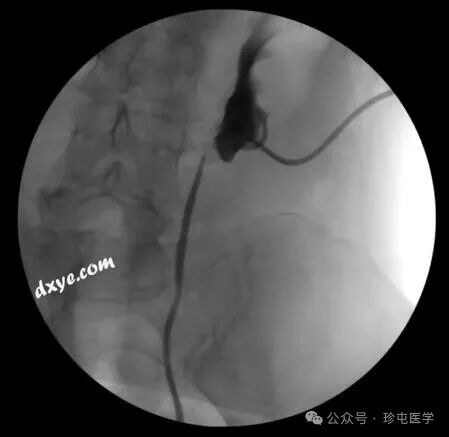

70F 有复发性 L UPJo 病史,s/p 之前接受过机器人 L 肾盂成形术,然后进行肾盂切开术 x2

腹部 CT 无造影显示手术夹靠近输尿管肾盂连接处 (UPJ)。从此图像很难判断手术夹是否正在侵蚀输尿管。

在手术中使用异物的一个并发症是可能侵蚀附近的组织。内窥镜切除侵蚀到尿道的异物是一种安全且微创的选择,以前已有描述,最常见于膀胱和尿道。介绍了一个有肾盂成形术病史的患者病例,发现有不同的异物侵蚀到输尿管并引起症状。据所知,这是第一例患者出现两种不同类型的输尿管异物侵蚀并分别通过内窥镜有效治疗的病例。